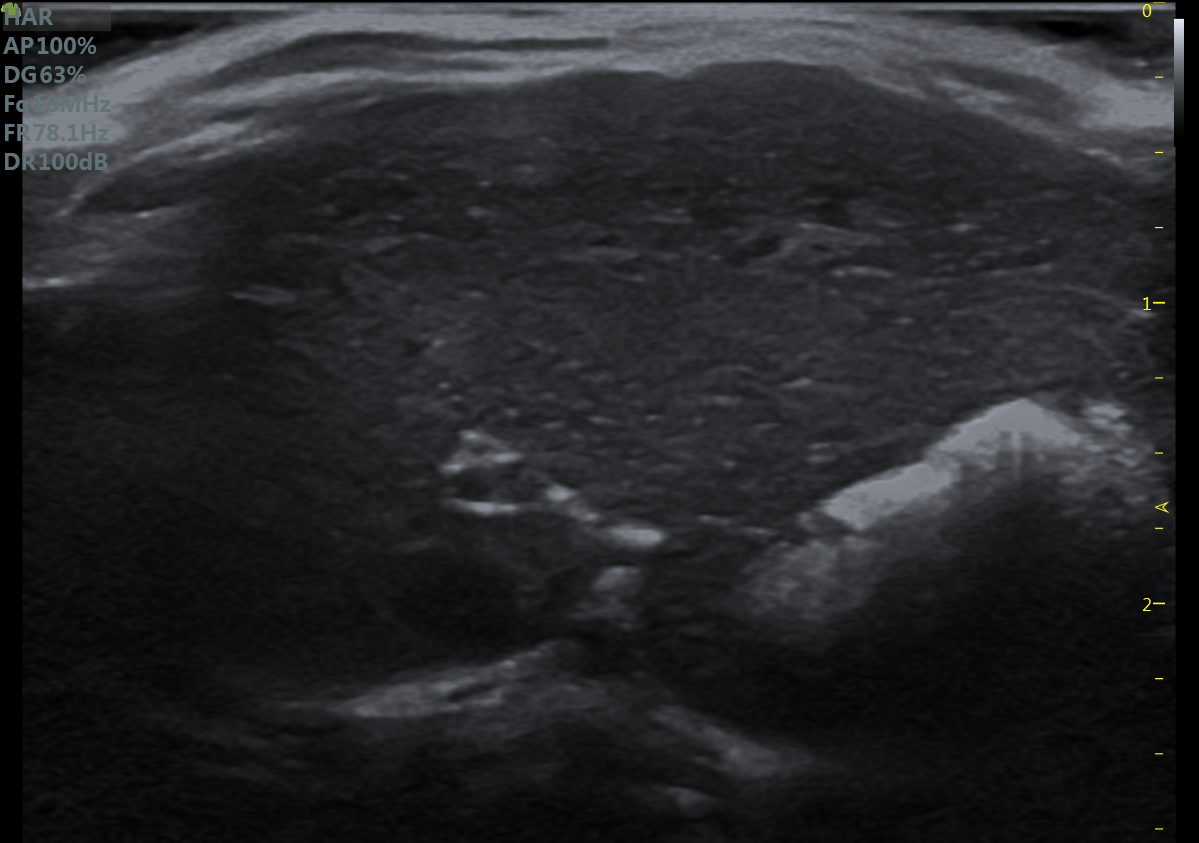

益仁恒业率先推出首款便携式小动物超声设备,它是专为实验小动物开发的高频高分辨率小动物超声成像系统,为研究者提供无创连续分析,高分辨率图像质量和组织结构和血流速度的定量分析。通过专门为小鼠和大鼠设计的硬件和软件,以及优化的人体工学操作设计,为研究人员在心血管研究,基因表达模式分析,肿瘤研究和药物开发等方面提供具有成本效益的应用工具。

23MHz高频探头,优秀卓越的浅表显影

小鼠乳头肌水平 小鼠肝脏

大鼠短轴M型 大鼠长轴M型

大鼠肝脏 大鼠肾脏